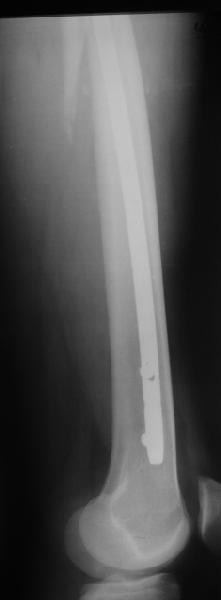

В диагноз пишем... Потом же как-то анализировать надо. Что-то никто не откликнулся на этот вопрос из англоязычных коллег. Все-таки - как такой перелом надо классифицировать? А если шейка бедра + диафиз? Завтра покажу такой случай.

Реконструкционный гвоздь.

Да, сейчас это и у нас самый напрашивающийся выбор. Сделали гвоздем ChM, картинки в приложении.

У молодых реконструкционный гвоздь самое то. При остеопорозе надо что-то помассивнее.